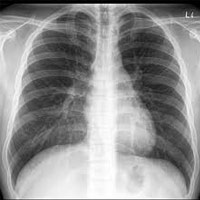

The plain postero-anterior (PA) chest film is the most frequently requested radiological examination. Visualisation of the lungs is excellent because of the incoherent contrast of the the tissues of the thorax.